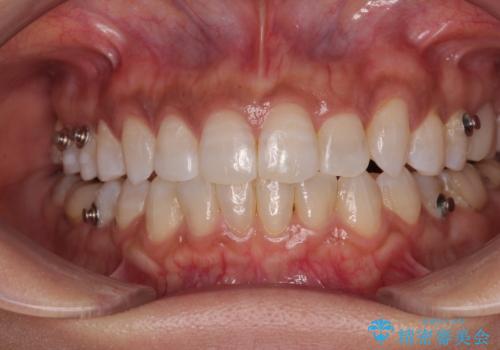

クロスバイトを治したい インビザラインによる矯正治療

- 前歯のクロスバイトを気にして来院された患者様です。

上下ともに、前歯部を中心にやや叢生が認められる程度であったため、ワイヤーでもインビザラインでも、どちらでも対応可能な状態でした。

咬合力が非常に強く、治療が進むにつれて上下奥歯が離開してくることが予想されるため、治療途中から上下の顎間ゴムを使用することを理解いただき、インビザラインによる矯正治療を行うこととしました。

咬合力による臼歯離開は顎間ゴムで改善されましたが、それとは別に下顎小臼歯がマウスピースに追従せず、補正のためのゴムかけが必要となりました。

大変なゴムかけ作業を頑張っていただき、無事に治療を終えることができました。